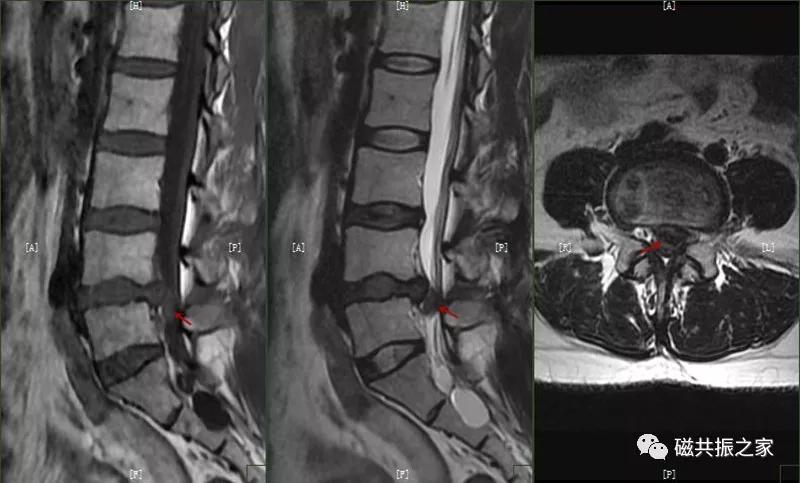

椎间盘脱出:椎间盘突出进一步发展,突出的髓核调入椎管内或与突出部分分离,先后移位形成脱出,甚至髓核可脱离进入椎管内,脱出的髓核在T1WI上呈低、等信号,在T2WI上呈中、高信号,需与椎管占位及滑膜囊肿鉴别。